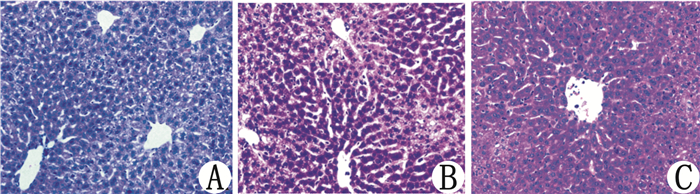

2.2 肝组织切片病理学变化在200×光镜下对比观察各组小鼠肝组织切片HE染色后的病理学变化。与对照组小鼠肝组织相比,LPS处理48 h的小鼠肝组织结构疏松,门管区炎性细胞浸润,胆小管增生,肝细胞空泡样变、嗜酸样变,局部出现点状坏死;与LPS组小鼠肝组织切片相比,LPS+MP组肝小叶结构相对完整,肝细胞空泡样变、嗜酸样变较LPS组小鼠明显减轻。健康对照组肝小叶结构完整,无肝细胞变性坏死(图 2)。

|

| A:Control组(健康对照组);B:LPS组(10 mg/kg LPS 48h处理组);C:LPS+MP组(20 mg/kg MP干预48 h组) 图 2 光镜下小鼠肝组织病理变化(HE×200) Figure 2 Histological changes of liver tissues(HE × 200) |